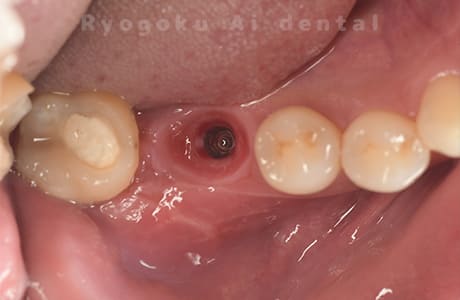

Case10

-

術前

術後

- 原因

- 左下6番欠損

- 治療内容

- インプラント治療

- 治療費用

- 約600,000円

左下の奥歯に歯を入れて欲しいとのことでご来院された患者様です。インプラント治療が最適とご提案させて頂き、治療を行いました。経過も良好で、大変満足して頂けました。

<リスク・副作用>

治療後、痛みや違和感、出血、腫れなどが出る事があります。喫煙者、糖尿病などの方の場合、歯が生着しない場合があります。